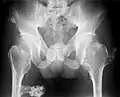

Multiple osteochondromas at the pelvis -

Multiple osteochondromas around the knee -